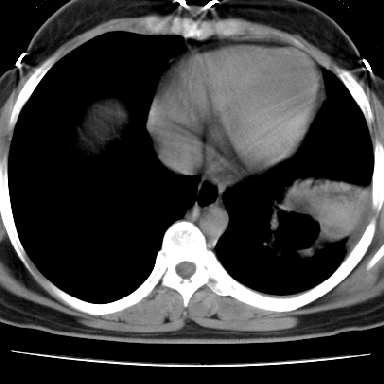

病灶与临床特点:1 位于下肺外围.2 与胸膜关系密切并明显胸膜反应.3 空洞内壁虽见壁结节,但还是较光滑.4 病灶周围明显渗出.5 另肺内多发小结节.6 临床症状轻,发病时间短.综合考虑:肺内特殊感染(霉菌感染).

1、癌性空洞,右肺小结节考虑转移。2、曲霉菌感染?右侧为播散